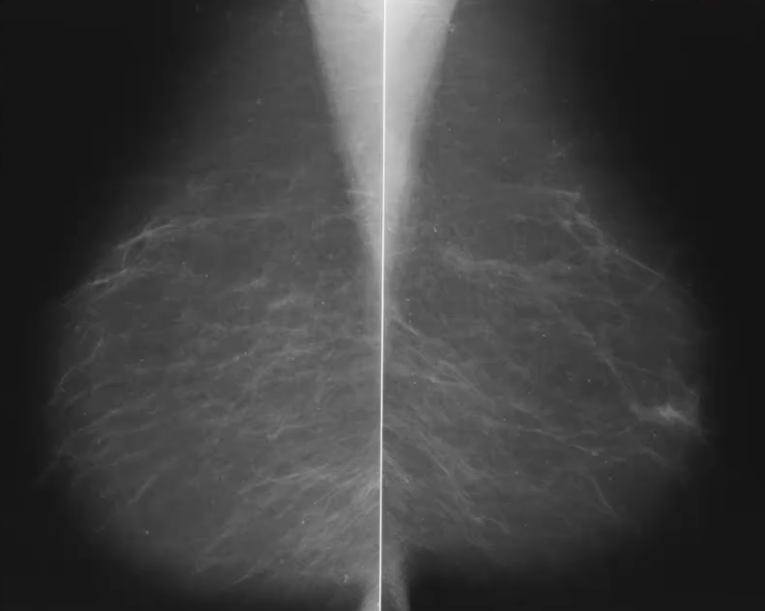

What is this an image of?

Fatty breast tissue

Dense breast tissue - more difficult to see breast cancers